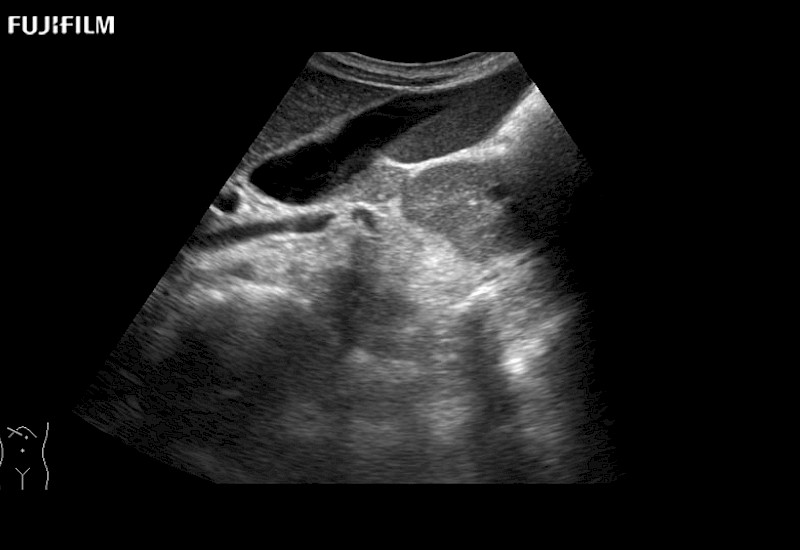

Fujifilm Healthcare understands that Surgical Oncologists demand excellence in their operating rooms — from their staff and the equipment they depend on. Fujifilm Healthcare's dedication to Surgical Oncologists provides outstanding ultrasound technology, professional support and the specialized tools necessary to best perform comprehensive real-time ultrasound imaging.

For precise surgical oncology ultrasound imaging, Fujifilm Healthcare offers premium level solutions that include:

for use during open and laparoscopic procedures: Tumor localization & staging, Ablation, Resection, Biopsy, Transplant, Abdominal exploration, Robotic surgery

Our dedication to Surgical Oncology allows us to offer superior image quality, outstanding system reliability and intuitive use of cutting edge technology.